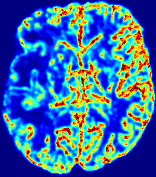

Slice #1Slice #2Slice #3Slice #4Slice #5Slice #6Dgtsuperscript𝐷gtD^{\text{gt}}Refer to captionRefer to captionRefer to captionRefer to captionRefer to captionRefer to caption(a)Refer to captionRefer to captionRefer to captionRefer to captionRefer to captionRefer to caption(b)Refer to captionRefer to captionRefer to captionRefer to captionRefer to captionRefer to caption(c)Refer to captionRefer to captionRefer to captionRefer to captionRefer to captionRefer to caption(d)Refer to captionRefer to captionRefer to captionRefer to captionRefer to captionRefer to caption(e)Refer to captionRefer to captionRefer to captionRefer to captionRefer to captionRefer to caption(f)Refer to captionRefer to captionRefer to captionRefer to captionRefer to captionRefer to captionRefer to caption000.060.060.060.120.120.120.180.180.180.240.240.240.300.300.30(mm2/s)𝑚superscript𝑚2𝑠(mm^{2}/s)

Figure 13: PIANO effectiveness and robustness testing: diffusion imaging via diffusion. Top row shows Dgtsuperscript𝐷gtD^{\text{gt}} used for simulating the ground truth pure diffusion. (a)-(f) refer to the results for D𝐷D estimated from the ground truth pure diffusion image time-series where Rician noise at levels 0%, 2%, 4%, 6%, 8%, 10% was added respectively.

Similarly, starting from the same initial condition C0superscript𝐶0C^{0} as in the ‘Advection Imaging’ experiment for each patient, we simulate concentration time-series {Cti(Ω)|i=0, 1,, 40}conditional-setsuperscript𝐶subscript𝑡𝑖Ω𝑖0140\{C^{t_{i}}\in\mathbb{R}(\Omega)|i=0,\,1,\,\ldots,\,40\} via a diffusion PDE, where we define the ground truth diffusivity D:=Dgtassign𝐷superscript𝐷gtD:=D^{\text{gt}} via the ADC map of the ISLES 2017 training set (ADC values are scaled by 0.000010.000010.00001 to ensure numerical stability):

Note this is likely not a spatially representative ground-truth for perfusion imaging, as it measures different effects from diffusion imaging. However, we still use it as a quasi-realistic pattern of diffusivity in the brain. We also added 2%, 4%, 6%, 8%, 10% levels of Rician noise to obtain simulations of ‘Diffusion Imaging’. The estimated Destsuperscript𝐷estD^{\text{est}} given concentrations of all noise levels for one patient are shown in Fig. 13, PIANO estimation results for all patients are summarized in Fig. 11 (b). Again, PIANO demonstrates its capability to recover the underlying diffusion field. In Fig. 13, when the noise level is increasing, some noisy patterns indeed appear in the associated Destsuperscript𝐷estD^{\text{est}}. Note that the ground truth diffusivity applied in this simulation experiment is about ten times larger than the diffusivity estimated in reality (Fig. 3, Fig. 4).